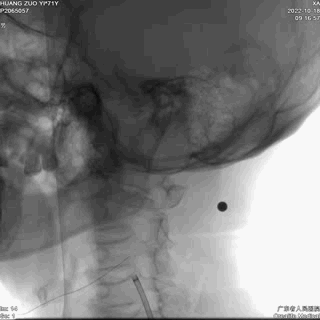

康德莱医械5F 125cm Simmons II+康德莱医械6F 900mm lonAccess长鞘同轴送达左侧颈总动脉末端。

动脉长鞘怎么置入【康德莱医械】经桡介入LA长鞘+Sim II通路组合处理颈内动脉狭窄_https://www.jmylbn.com_新闻资讯_第19张

动脉长鞘怎么置入【康德莱医械】经桡介入LA长鞘+Sim II通路组合处理颈内动脉狭窄_https://www.jmylbn.com_新闻资讯_第20张

➤ 沿康德莱医械6F lonAccess长鞘同轴送入Filterwire远端血栓保护装置至左侧颈内动脉C1段远端,定位准确后释放血栓保护装置。